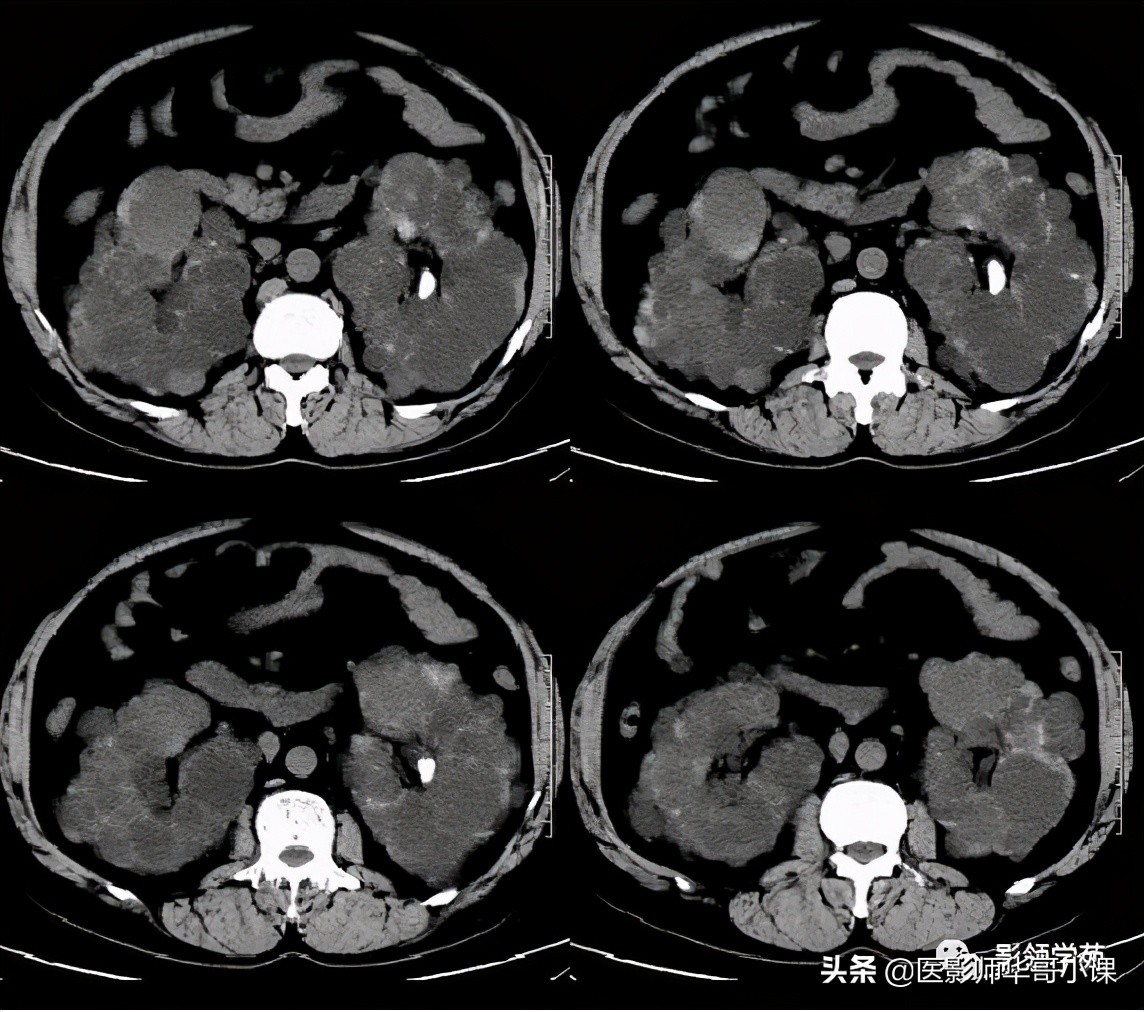

- 由于本病常合并存在其他器官的囊性病变,应该同时了解肾脏、胰腺、脾脏是否也有囊性改变。

1、肝内胆管不成比例的扩张,并与正常胆管相间,这是鉴别本病与继发性阻塞性肝内胆管扩张的关键所在,后者表现为从中央向末梢逐渐变细的、成比例的扩张。

2)多囊肝:常染色体显性遗传,也常合并多囊肾。临床无症状,囊腔形态多数较规则,不与胆管相通,胆管不扩张,无“中心点征”。